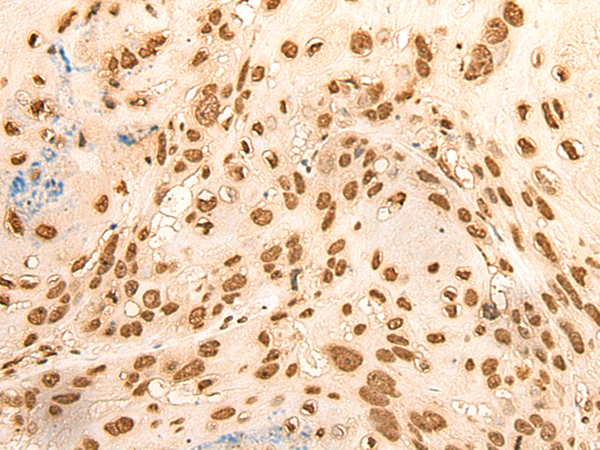

IHC positive control:

Human esophagus cancer and Human liver cancer

IHC Recommend dilution:

30-150